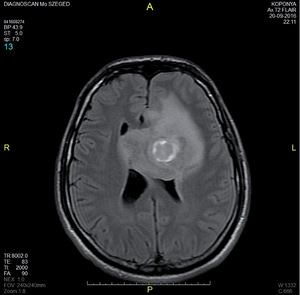

3.6.2. Daganatok: az agy (64–72. ábra)

- MRI: T2, FLAIR, T1/T1gad, DWI.